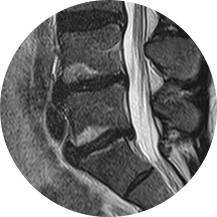

MRI of lower spine.

Find a doctor who specializes in the diagnosis and treatment of vertebrogenic pain with the Intracept Procedure. If you haven’t had an MRI recently, your doctor may require that you get one prior to the appointment.